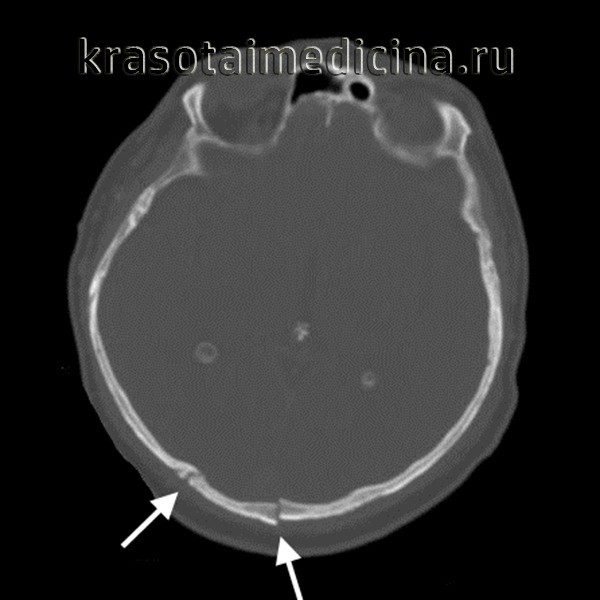

КТ головы (3D-реконструкция). Перелом лицевого черепа (скуловой дуги) и перелом в области лобно-скулового шва.